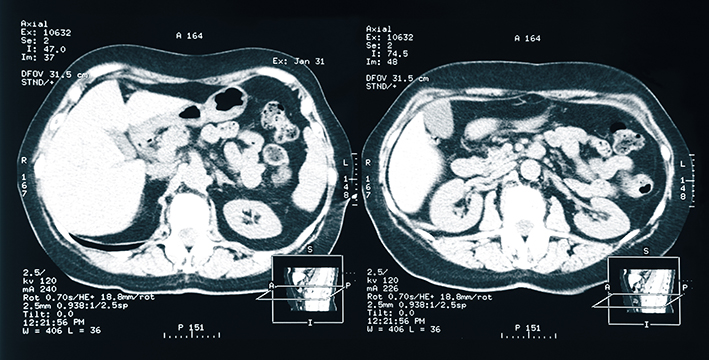

Die akute Nierenschädigung ist eine häufige Komplikation bei PatientInnen auf Intensivstationen und ist mit einem hohen Risiko für Tod, Folgekomplikationen und Ressourcenverbrauch verbunden. Viele dieser PatientInnen erhalten eine Nierenersatztherapie. Diese wird zur Behandlung schwerwiegender Stoffwechselstörungen (z.B. Azidose, Hyperkaliämie, Urämie) und Störungen im Flüssigkeitshaushalt benötigt (Überwässerung). Nach wie vor ist es jedoch unklar, wann genau mit einer Nierenersatztherapie begonnen werden soll.

Auch in der aktuellen COVID-19 Pandemie zeigt sich, dass viele kritisch kranke PatientInnen mit COVID-19 zusätzlich eine akute Nierenschädigung entwickeln. Im Tiroler COVID-19 Intensivmedizin Register (Koordinatoren Michael Joannidis, Sebastian Klein) zeigte sich bei 106 IntensivpatientInnen mit COVID-19, dass beinahe die Hälfte dieser PatientInnen eine akute Nierenschädigung aufwies. Knapp 20 Prozent benötigten weiterführend eine Nierenersatztherapie. (Das Manuskript zur Publikation ist eingereicht)